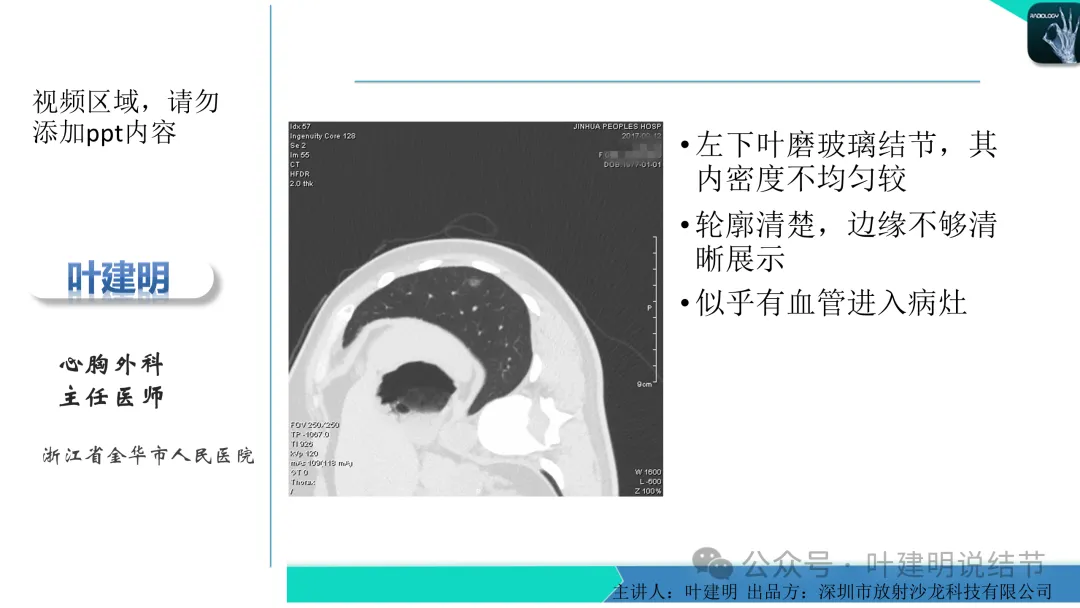

当地说考虑微浸润性腺癌的左下主病灶影像连续层面展示:

病灶出现,显模糊。

上图层面轮廓较清,但密度很淡,似见血管走行,但靠左前方的似条状磨玻璃密度与血管连着的到底是血管分支还是结节的一部分,其实并不确切。如果其实是血管分支,那病灶与它之间就不是空泡。

病灶在此层整体边缘显糊,灶内有空泡似的,瘤肺边界欠清。

边缘不平,还是灶内多发小空泡?邻近血管与之紧贴,但血管无异常走行。病灶密度很低,显糊。

中间所谓空泡更像是细支气管扩张,内壁非常光滑且圆形。

病灶边缘区淡而模糊。